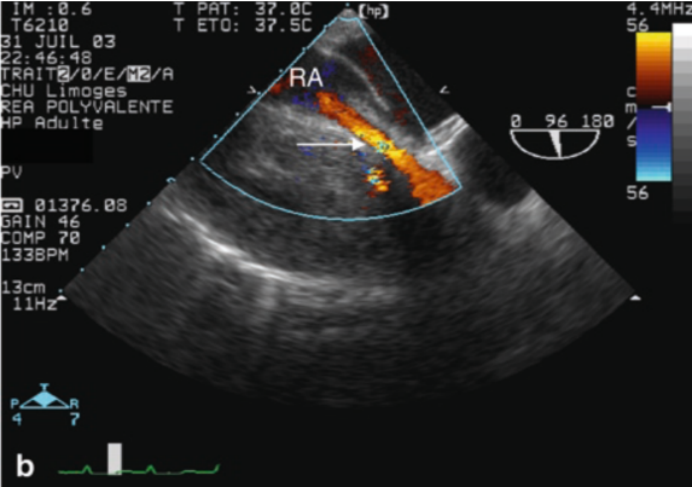

此外,还有一些特殊情况,例如:外科术后出现心包内血肿、纵隔血肿,心包粘连、肿瘤,都可能导致超声图像不典型,需要经食道超声辅助(图6,图7)

图片

6  经食道超声显示心包内巨大血肿

7  右心房被血肿压迫,血流信号减少